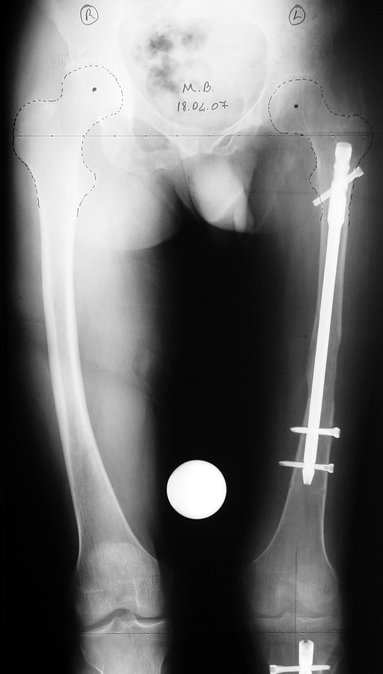

3- POSTTRAVMATİK BACAK KISALIĞI (YANLIŞ KAYNAMA)

Bu Bacak Kısalık tipi bir kırığın kısalmış pozisyonda kaynaması ile oluşur. Bir çok vaka yetişkinlerde görülür ve sadece bir uzatma ile tedavi edilebilir. Ek deformiteler de aynı anda düzeltilebilir. Bu hastaların çoğu çivi üzerinden uzatma veya tam implante edilen çivi ile tedavi edilebilirler.